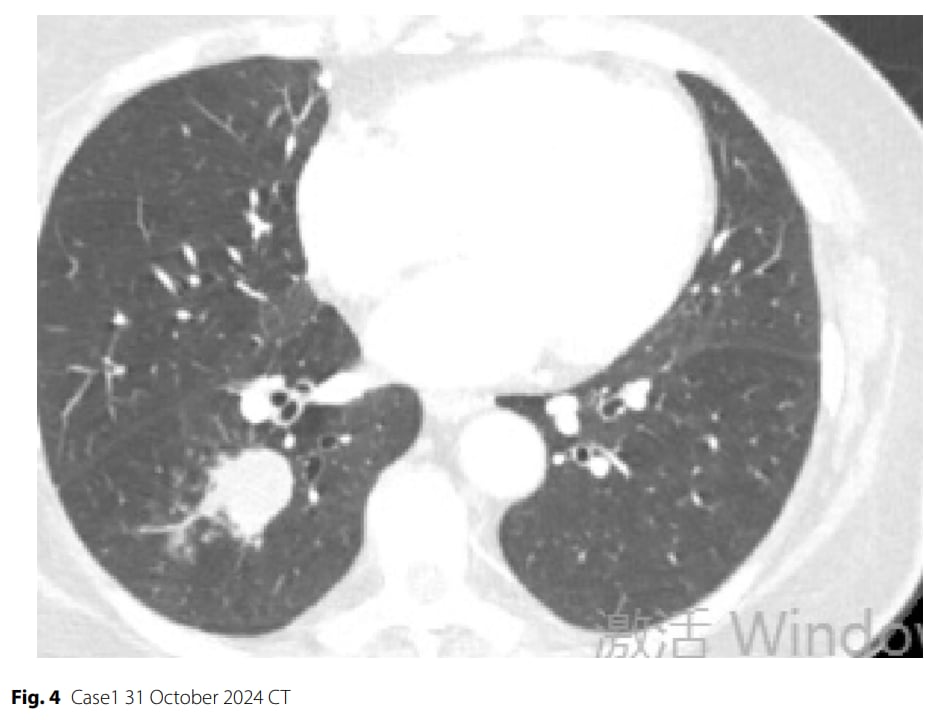

▲图4 病例1 2024年10月31日CT

治疗过程:患者接受了3个周期的“依托泊苷+卡铂+斯鲁利单抗”新辅助治疗。治疗后,肿瘤标志物迅速恢复正常,影像学检查显示肿瘤部分缓解(缩小超过30%)。经多学科团队会诊,患者强烈要求手术,并结合现有研究证据,认为此时进行手术可能是最佳策略。随后患者接受了右肺下叶切除术。

- 病理完全缓解(pCR):术后病理检查令人惊喜,原发灶及所有淋巴结均未发现癌细胞残留,达到了最理想的病理完全缓解。

- 分子标志物显著改善:术后分子分析显示,PTEN突变频率从30%降至1.50%,肿瘤突变负荷(TMB)更是从治疗前的17.65个突变/兆碱基完全降至无法检测水平(0.00个突变/兆碱基)。PD-L1表达阴性(TPS/CPS=0%)。